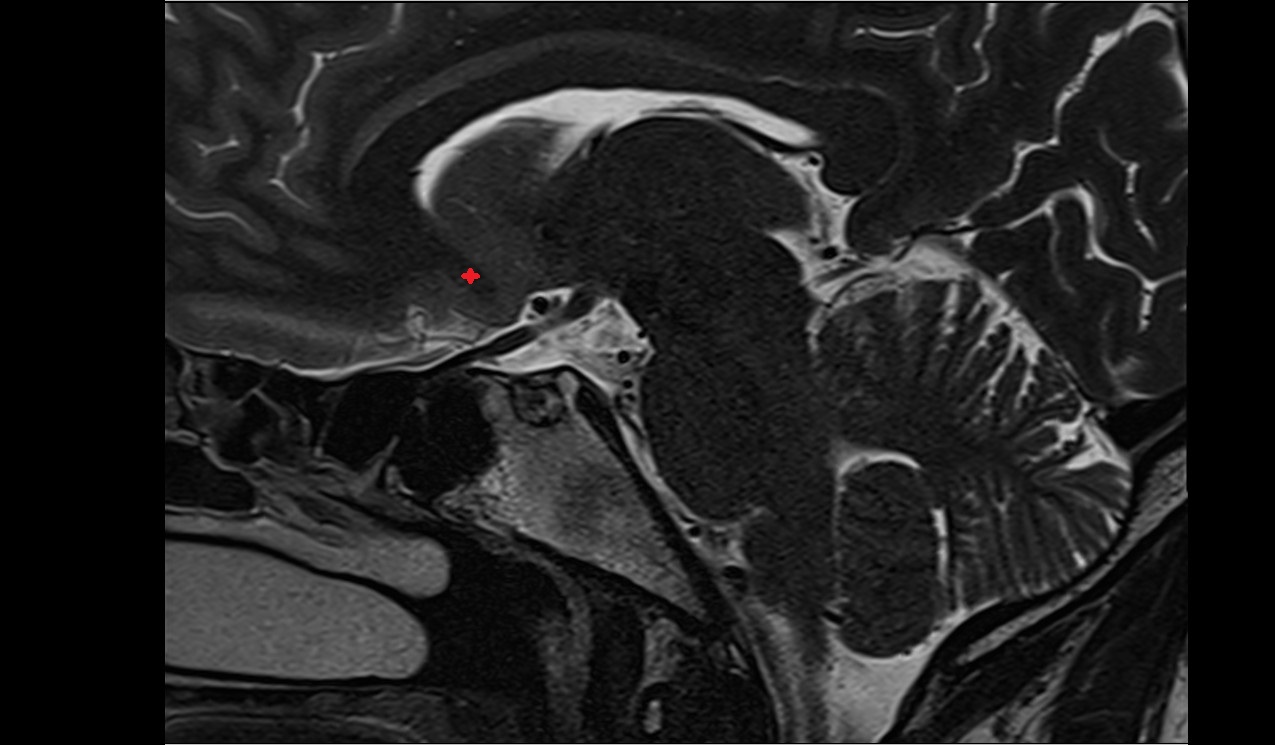

- Temporomandibular joint

- Mandibular condyle

- Mandibular fossa

- Articular disc of temporomandibular joint

- Articular eminence

- Superior head of lateral pterygoid muscle

- Inferior head of lateral pterygoid muscle